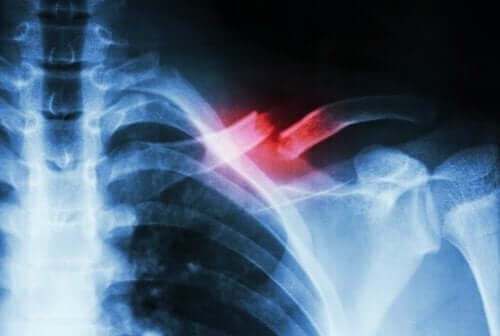

Een stressfractuur treedt op wanneer er een kleine, incomplete breuk in een bot van het skelet ontstaat die veroorzaakt wordt door iets anders dan een sterke klap. Meestal ontstaat dit letsel door repetitieve bewegingen of door een snelle toename van de hoeveelheid en/of intensiteit van een activiteit.

Dit soort fracturen is niet eenvoudig te diagnosticeren. Daarom vereisen ze een bezoek aan een medisch specialist en aanvullende tests om het te onderscheiden van andere aandoeningen. Dit komt omdat de breuk meestal niet wordt gedetecteerd op een röntgenfoto.

Een stressfractuur is een incomplete breuk die kan optreden als gevolg van de overbelasting door een fysieke activiteit. Wanneer er geen continuïteit in het botweefsel is, is er sprake van een breuk.

Een stressfractuur is eigenlijk een soort splinter of een incomplete scheur van het bot. Het ontstaat als gevolg van herhaald microtrauma of overbelasting, zoals we hierboven reeds aangaven. Bovendien kan een stressfractuur ernstige pijn veroorzaken bij het uitvoeren van bepaalde fysieke activiteiten. Vaak verdwijnen ze wanneer de activiteiten gestopt worden.